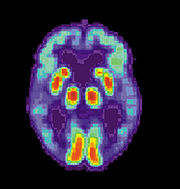

Alzheimer's disease is characterised by loss of neurons and synapses in the cerebral cortex and certain subcortical regions. This loss results in gross atrophy of the affected regions, including degeneration in the temporal lobe and parietal lobe, and parts of the frontal cortex and cingulate gyrus. Studies using MRI and positron emission tomography have documented reductions in the size of specific brain regions in patients as they progressed from mild cognitive impairment to Alzheimer's disease, and in comparison with similar images from healthy older adults.

When available as a diagnostic tool, SPECT and PET neuroimaging are used to confirm a diagnosis of Alzheimer's in conjunction with evaluations involving mental status examination.In a person already having dementia, SPECT appears to be superior in differentiating Alzheimer's disease from other possible causes, compared with the usual attempts employing mental testing and medical history analysis. Another recent objective marker of the disease is the analysis of cerebrospinal fluid for amyloid beta or tau proteins. Both advances have led to the proposal of new diagnostic criteria. A new technique known as PiB PET has been developed for directly and clearly imaging beta-amyloid deposits in vivo using a tracer that binds selectively to the Abeta deposits. Recent studies suggest that PIB-PET is 86% accurate in predicting which people with mild cognitive impairment will develop Alzheimer's disease within two years, and 92% accurate in ruling out the likelihood of developing Alzheimer's. Volumetric MRI, which can detect changes in the size of brain regions that atrophy during the progress of Alzheimer's disease, is also showing promise as a diagnostic method. It may prove less expensive than other imaging methods currently under study.